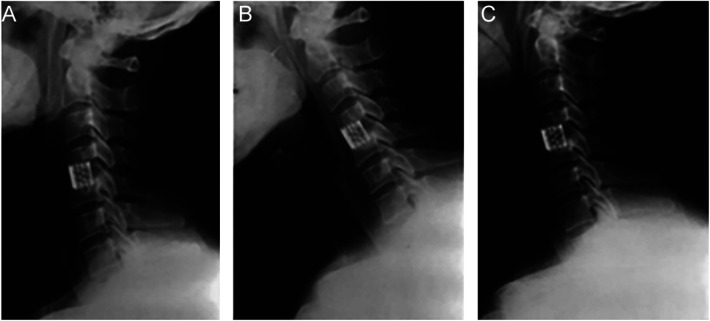

Abstract Image